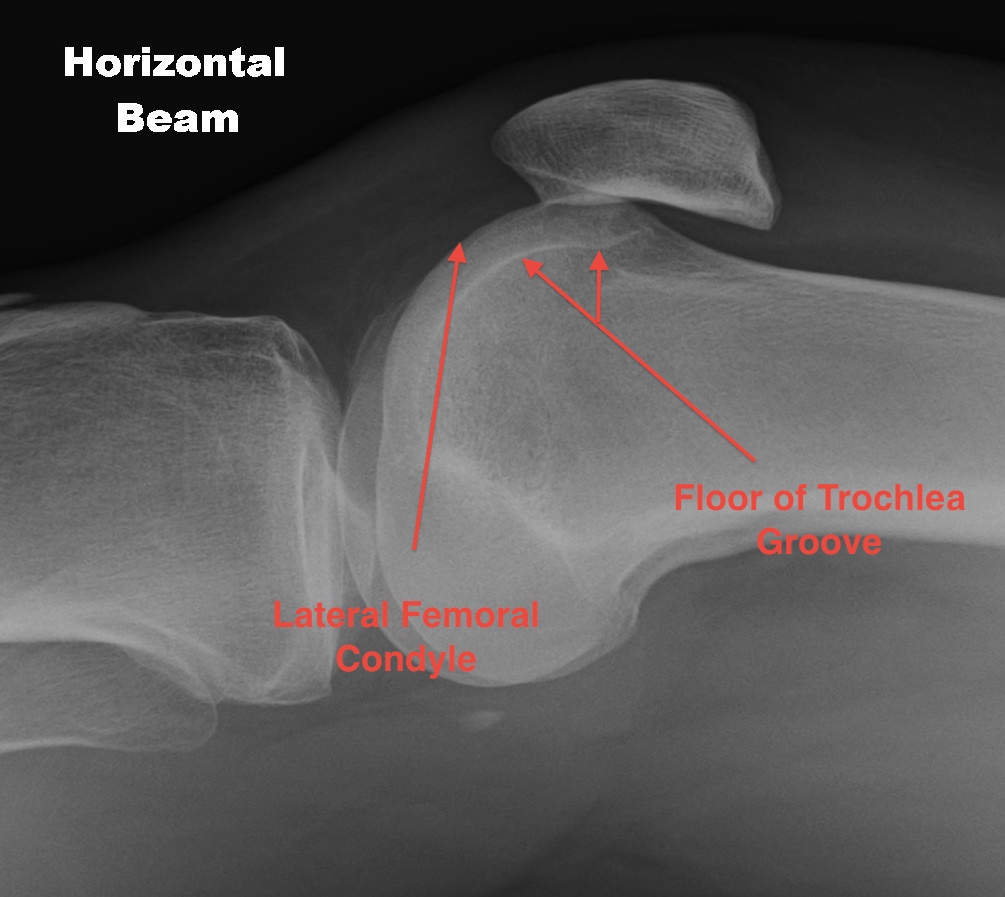

Dejour Crossover Sign

- lateral x-ray at 30o with condyles superimposed

- identify base of trochlea

Normal

- clearly defined trochlea groove

Abnormal / Crossover

- line of floor of trochlea crosses lateral lip of condyle

- indicates trochlea is deficient proximally